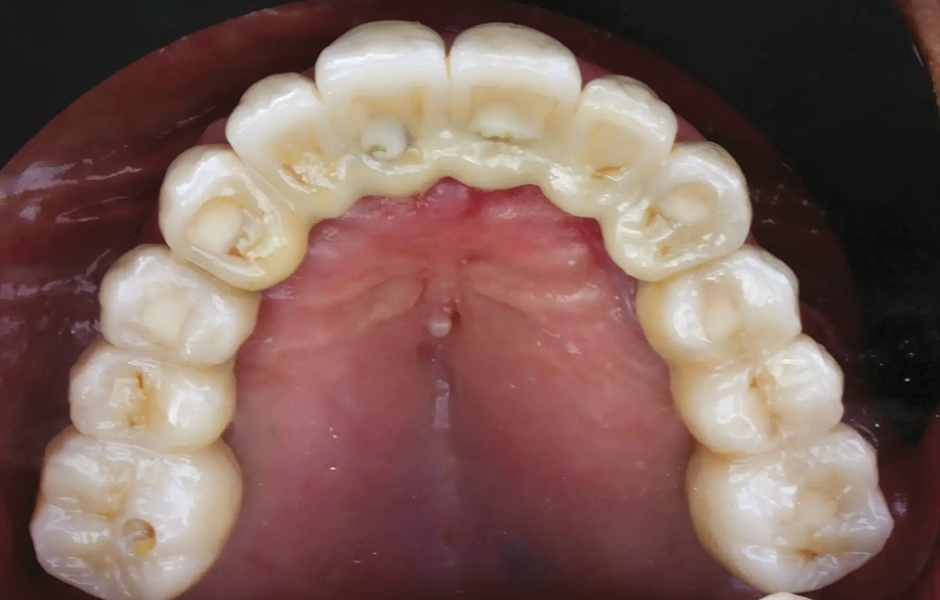

Při finální návštěvě byla nasazena definitivní hybridní šroubem fixovaná protetika. Definitivní práce sestávala z CAD/CAM titanového skeletu přišroubovaného na všechny implantáty a tří monolitických zirkoniových segmentů vlepených nahoře (obr. 18a–c). Byla zkontrolována okluze a pacient byl zařazen do čtyřměsíčního recall programu. Při poslední kontrole (rok po implantaci) byly všechny implantáty úspěšné a pacient byl plně spokojen s novou protetikou (obr. 19–22).

Obr. 20: Definitivní protetická práce při jednoroční kontrole, okluzální pohled.